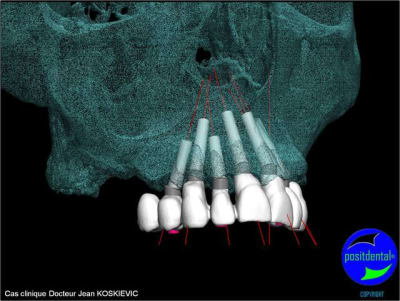

Montage esthétique ou wax-up 3D

et la projet 10 implants maxillaire sup

10 en haut